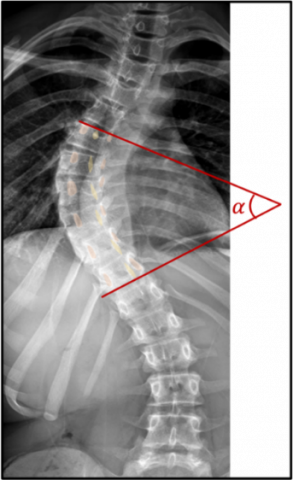

The Gold Standard in the diagnosis of scoliosis is the radiography of the spine. It is based on two criterions obtained on the frontal radiography: Asymmetries on the vertebral pedicles (proof of an axial deformation) and a Cobb angle (angle between the line drawn on the upper end plate of the most tilted vertebra above the apex of the curvature and the lower end plate of the vertebra under the curvature’s apex) higher than 10°, proof of a significative deviation in the frontal plane (Figure 1). Different levels of severity can be established with this diagnosis.

Figure 1. The Cobb angle is the α angle evaluated on this radiography of the spine in the frontal plane

The management of scoliosis depends mainly on its severity [1]. It consists in rehabilitation, for low Cobb angles (<10°), which still does not constitute a "true scoliosis" from the point of view of diagnostic criterions. Patient with a more severe scoliosis will have to wear a brace combined with rehabilitation, for Cobb angles between 10 and 25°. For Cobb angles above 25°, there will be discussion of surgery with rehabilitation because the above-mentioned non-invasive techniques are usually insufficient to correct the deformity.